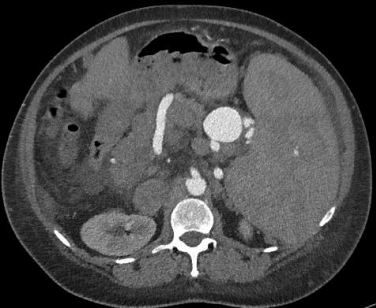

多排螺旋CT增强扫描是诊断SAA和其他内脏动脉瘤的理想影像学检查方法。CT有助于发现小SAAs并评估解剖结构,为手术规划提供依据。

磁共振成像(MRI)是CT的替代方法,尤其是在慢性肾功能不全患者中。 对比血管造影(Contrast angiography, CA)是识别SAAs最特异的影像学检查,也可能具有治疗作用。 超声内镜可以可靠地鉴别SAAs与胰腺假性囊肿等其他外源性病变 | ||||||||